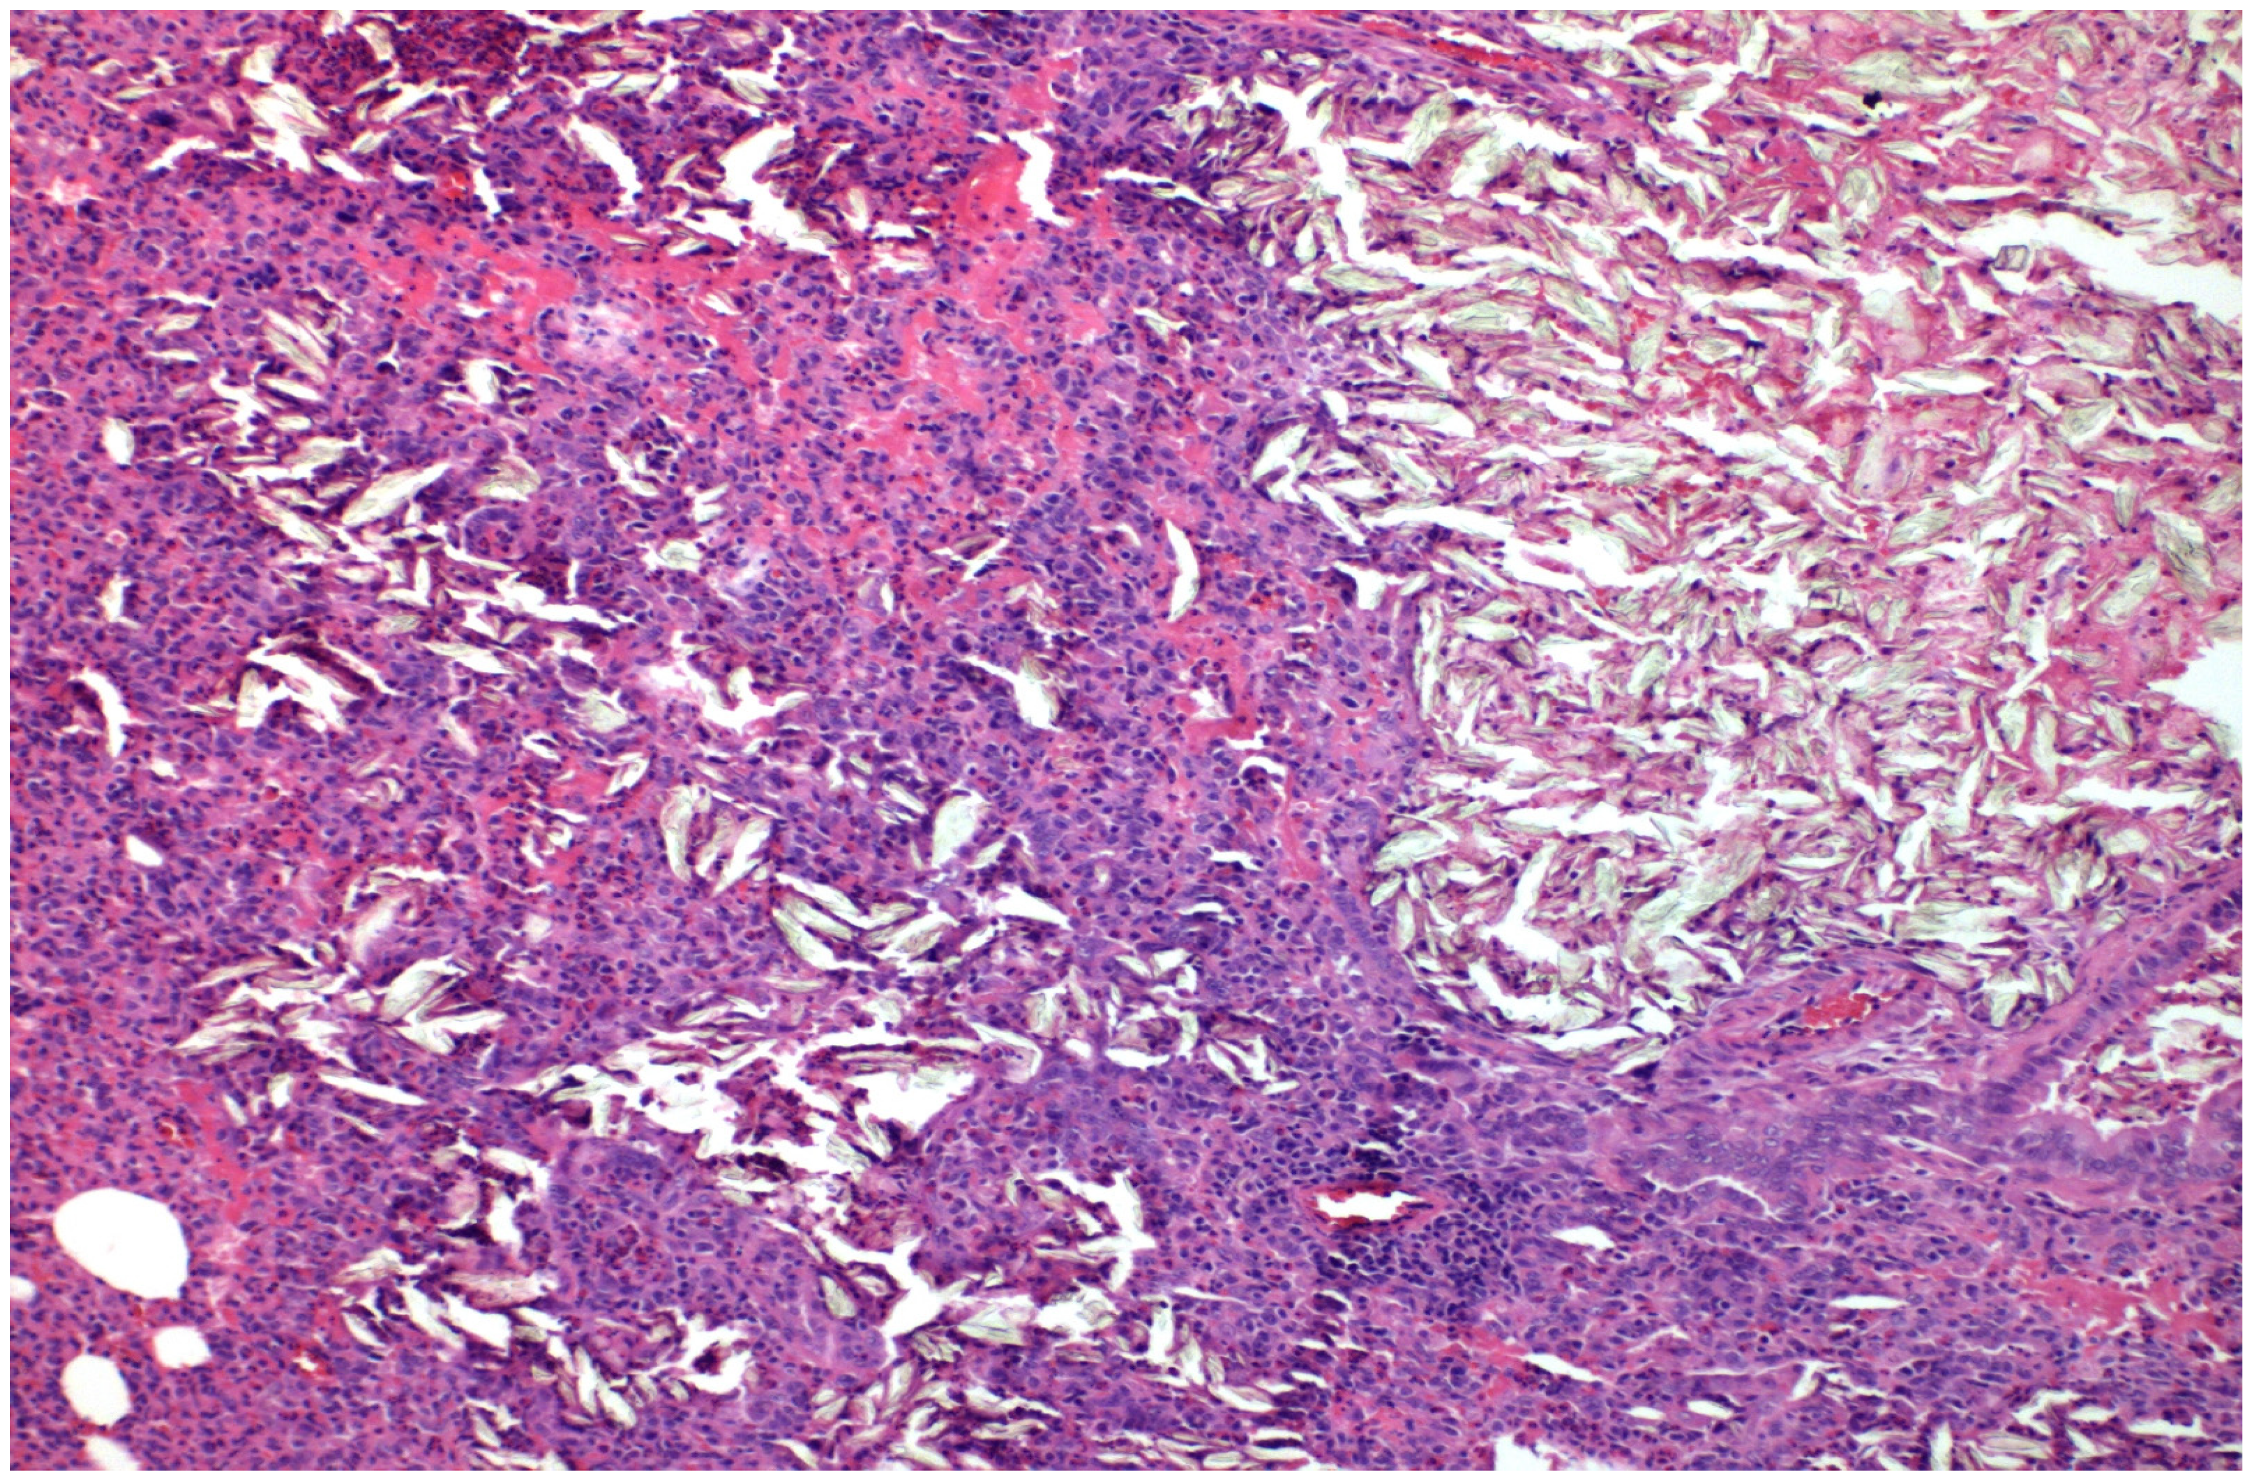

- With talc, there was a statistically significant difference in the inflammation provoked in 6 days compared to 3 days regarding parietal pleura (p = 0.002) (Figure 11); regarding visceral pleura, this could not be measured, as inflammation was high in both groups (grade II–III).